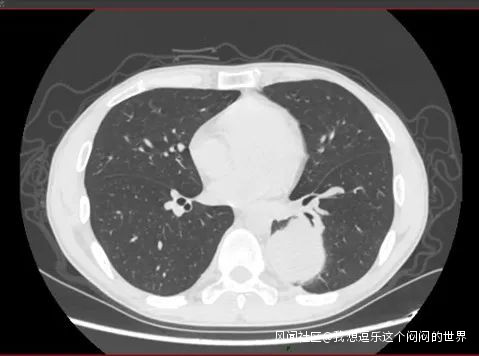

病例1,男,43歲。因“咳嗽咳痰1月餘”在3月份至我院門診就診,行胸部CT檢查發現左下肺巨大佔位。

左下肺佔位,直徑約6cm

這種大小的腫塊基本上考慮是惡性腫瘤,正常流程是要入院明確診斷,然後評估診療方案的。如果淋巴結沒有轉移,或者只有N1(肺門淋巴結)的轉移,是可以考慮直接手術的。